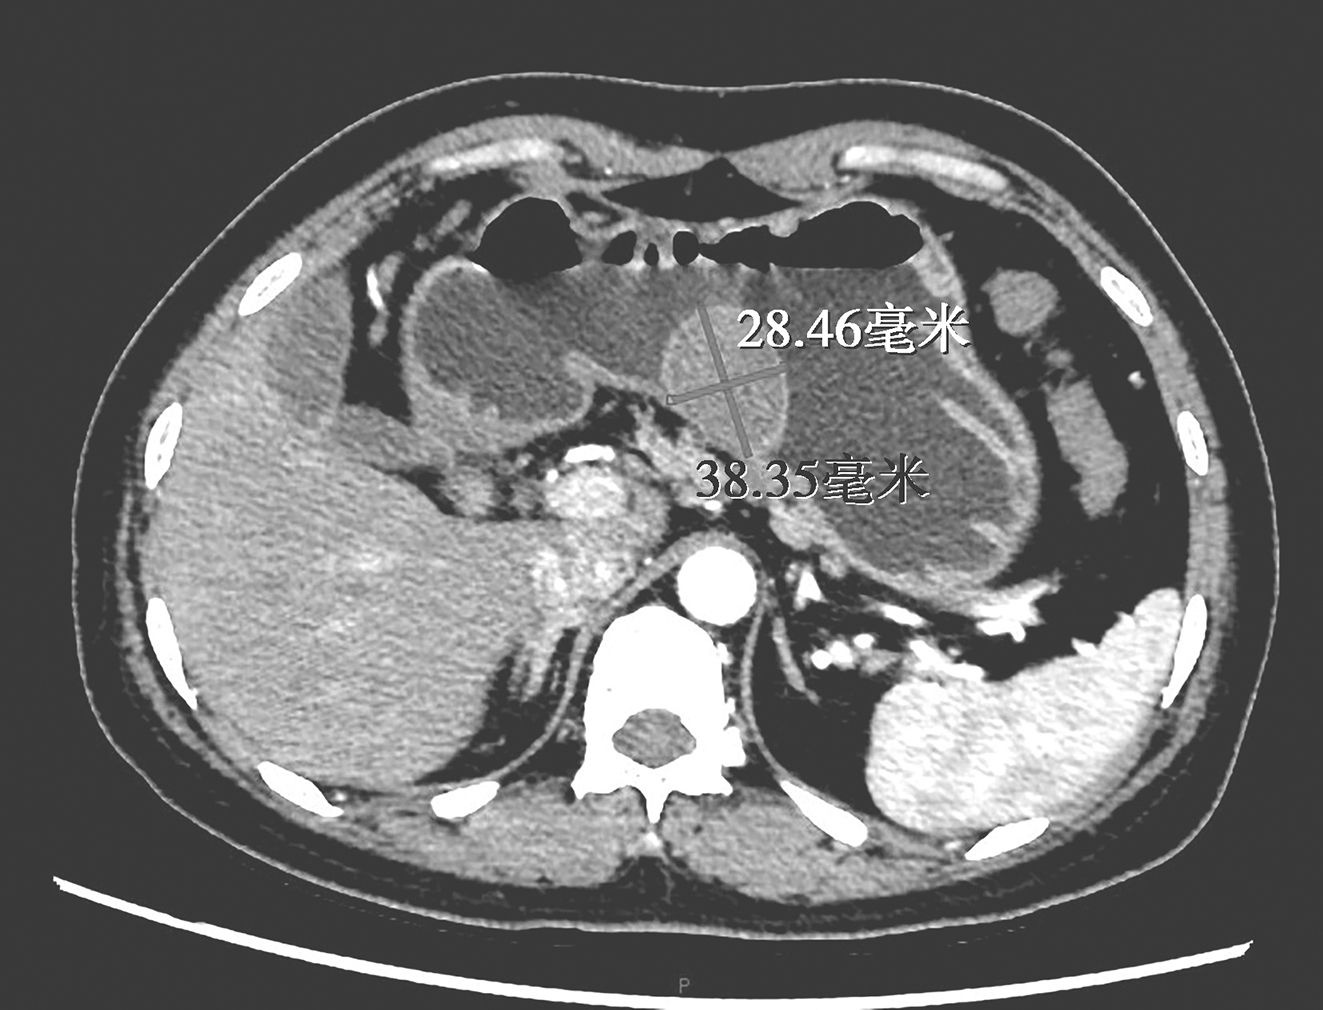

胃增强CT:胃体小弯侧占位,CT表现倾向于黏膜下来源,考虑GIST可能大,建议结合内镜及病理结果。肝脏多发微小囊肿。胆囊腺肌症。扫及两侧胸腔少量积液(图2)。

图2 CT提示胃体小弯侧占位